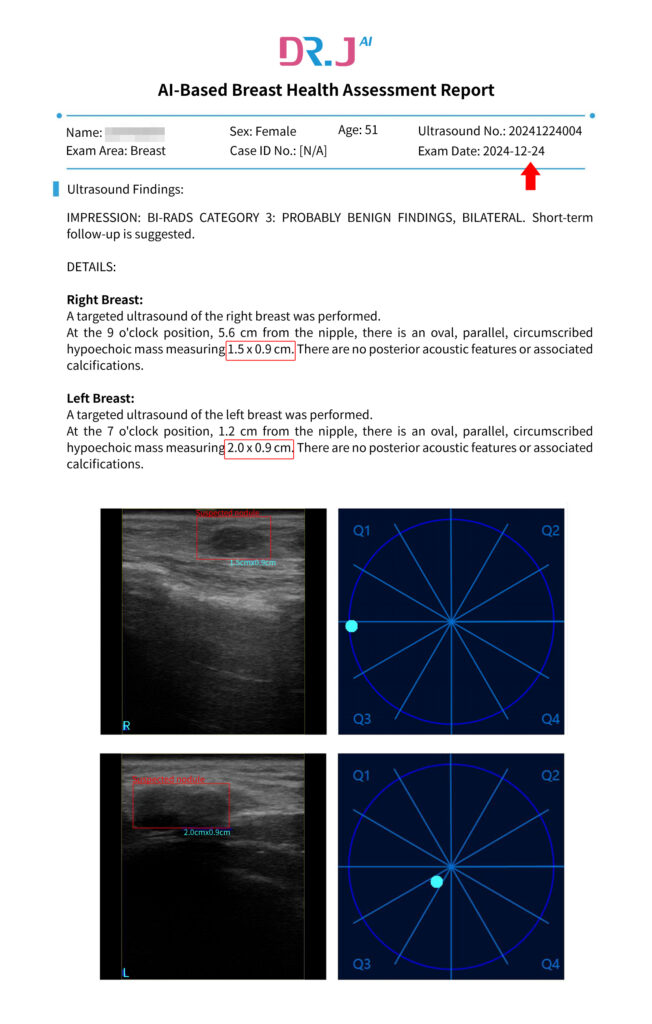

- Client profile: Lily Wang, a 51-year-old woman proactively concerned about her breast wellness.

- Initial assessment (by Dr. J AI): On Dec 24, 2024, the AI detected multiple concerns, including a 19.9mm x 9.2mm nodule.

Such was the case for Lily Wang. On Dec 24, 2024, she underwent a Dr. J AI Breast Health Assessment at her trusted salon. The report flagged several “areas of concern,” the largest being a 19.9mm x 9.2mm nodule.